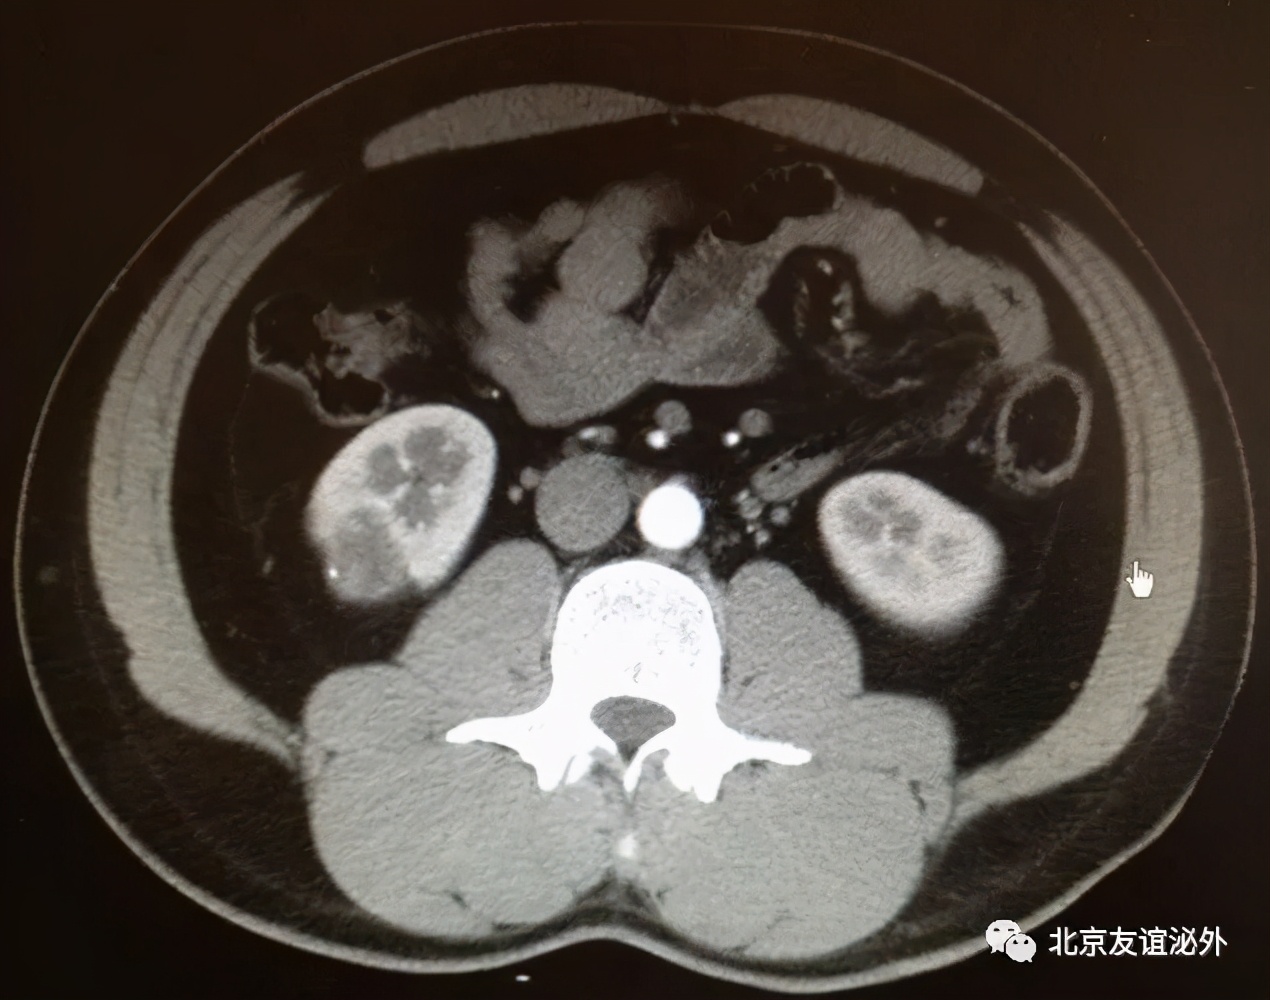

图2. Bosniak I级恶性囊肿(肾透明细胞癌),临床极为少见